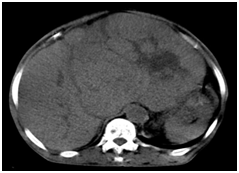

Abdominal CT scan was performed in 79 patients (34%). It was performed in conjunction with ultrasound in 71 patients (90%). There was hepatomegaly in 70 patients (88.6%). The nodules were noted in 76 cases (96.2%), with an average size of 98.9 mm (range 13 to 223 mm). The distribution of lesions according to the number of nodule and headquartered in CT is noted in Table 2. Early contrast enhancement during the arterial phase, with a washing portal phase was present in 61 cases (77.2%) Figure 2. These aspects were not specified in 16 cases (20.2%). The nodules were hypo‒vascular in 2 cases (2.6%). The effusion intraperitoneal was visualized in 30 cases (38%). The presence of a venous invasion was noted in 22 cases (27.8%). Deep adenomegalies were present in 9 cases (11.4%). The alpha‒fetoprotein levels were performed in 230 cases (88.1%). The rate was very suggestive in 174 cases (75.7%), reminiscent in 38 cases (16.5%) and negative in 18 cases (7.8%). Histological confirmation was performed in 44 cases (18.8%). Hepatocellular carcinomas (HCC) accounted for the majority of the lesions found in 42 cases (95.5%). Of these lesions, 33 were poorly differentiated, moderately differentiated 4 and 5 well differentiated. We also noted one case of fibro‒lamellar carcinoma and 1 case of cholangio carcinoma. The staging had identified 18 cases (8%) of lung metastases (13 cases of 37 chest X‒ray front and 5 cases of 7 chest CT).

Figure 2 Axial cuts in CT scan of liver.

1. Without contrast. Tissular heterogenous masse in the left liver isodense compared to the rest of the liver.

2. After contrast injection in arterial phase. The tumor is hypervascularized compared to the rest of the liver.

3. After contrast injection in venous phase. The tumor appears hypodense compared to the rest of the liver (wash out).